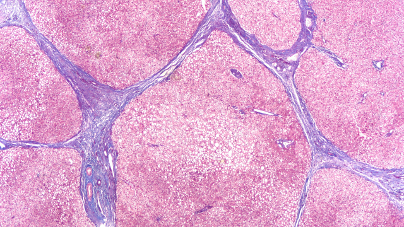

美国食品药品监督管理局(FDA)已批准勃林格殷格翰公司的“贾赛迪”(奈瑞曼利斯特)片剂用于治疗特发性肺纤维化(IPF)。贾赛迪的获批使其成为近 10 年来首个获批用于治疗 IPF 的新疗法。由于 IPF 是一种罕见、严重且不断恶化的疾病,目前尚无治愈方法且治疗手段有限,此次获批标志着为那些患有该疾病的人提供支持的重要一步。